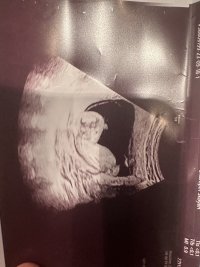

Litt uklart bilde, men tipper gutt. Det jeg tror er nub har litt høy vinkel til å være jente. Har du flere bilder i andre vinkler?Lyst til å gjette?Bilde fra uke 13+0. Vet ikke om nuben synes så godt men

Litt uklart bilde, men tipper gutt. Det jeg tror er nub har litt høy vinkel til å være jente. Har du flere bilder i andre vinkler?

Tipper guttNoen som klarer tyde nub her? 12+5